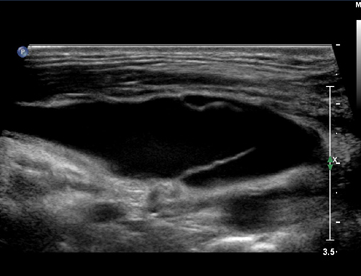

隐-腘静脉汇合处(SPJ)解剖示意图.

小隐静脉可不通过隐腘交界处直接移行为Giacomini静脉,上图所示为正常的SPJ结构与Giacomini静脉